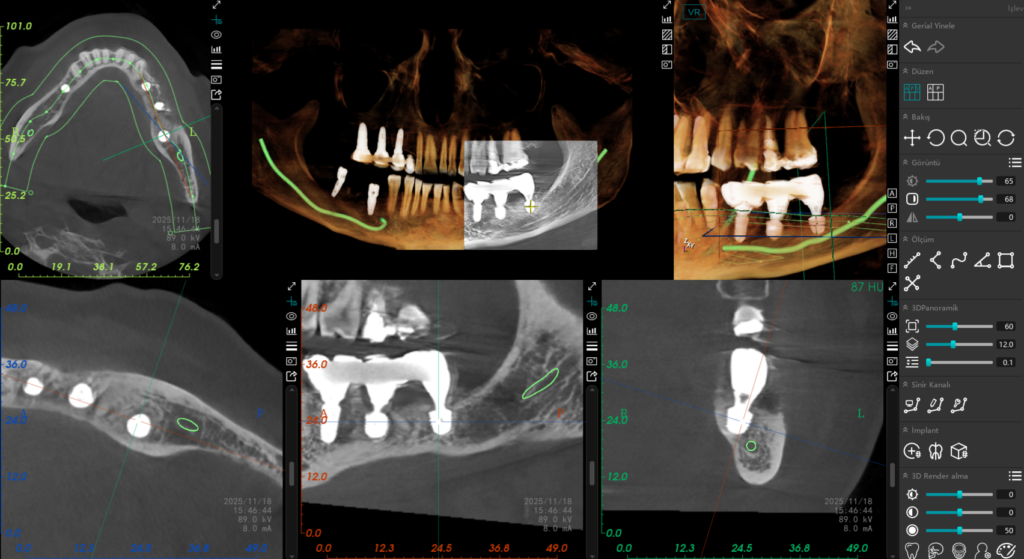

Alt çenede ana sinir kanalına olan mesafe kısıtlı (5-6 mm) olduğunda, geleneksel uzun implantlar büyük bir risk teşkil eder. Bu vakada, Alman mühendisliğinin güvenilir çözümü olan Bredent short (kısa) implantları tercih ettim. Bu özel tasarım implantlar sayesinde, sinir kanalına güvenli bir mesafede kalarak, hastamızı olası bir his kaybı riskinden tamamen korumuş olduk.

Sadece implant yerleştirmekle yetinmeyip, bölgedeki doku kalitesini de artırmayı hedefledim. Hastamızın kendi kanından elde ettiğimiz PRF (Trombositten Zengin Fibrin) ile hazırladığımız “Sticky Bone” yapısını kullanarak cerrahi bölgede stratejik bir augmentasyon (kemik hacmi artışı) sağladık. Bu biyolojik yaklaşım hem iyileşmeyi hızlandırdı hem de implant çevresindeki doku desteğini maksimuma çıkardı.